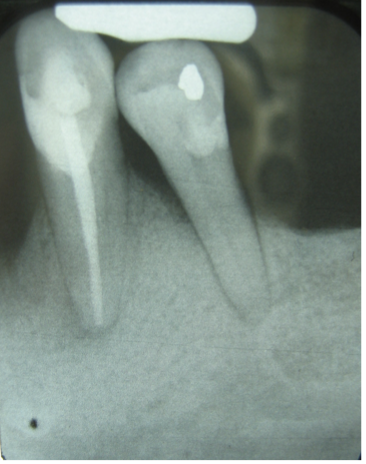

Here are two mandibular teeth, #22 and #20. #21 is missing. Which of the following is true from the information you can see in this radiograph?

a) the ideal crown to root ratio can be seen in tooth #22

b) the crown to root ratio for #20 makes it recommended as a bridge abutment

c) the conical root shape of #22 enhances the actual area of support more than expected from the height of the bone

d) an endodontic assessment of #22 is not necessary before the definitive treatment plan

e) all of the answers are incorrect

f) all of the answers are correct

A